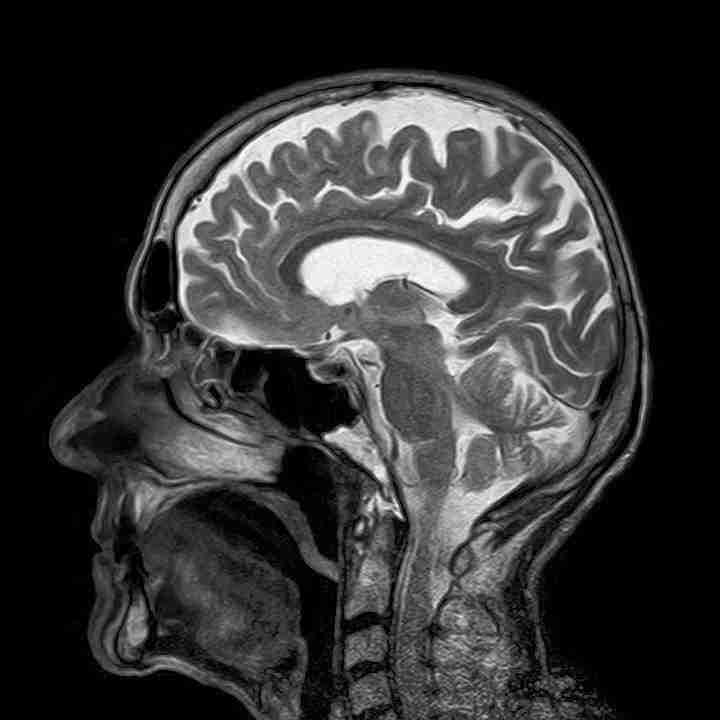

Ahora puedes leer el artículo de La Voz del Muro sobre Privación de Sueño Ocasiona Que El Cerebro Se “Coma A Si Mismo”.

Un nuevo estudio sugiere que la privación crónica del sueño puede hacer que el cerebro “se coma a si mismo” a medida que las células que digieren sus desechos entran en sobremarcha.

Como todos sabemos, dormir es crucial para el buen funcionamiento del cerebro. Mientras dormimos, los desechos…